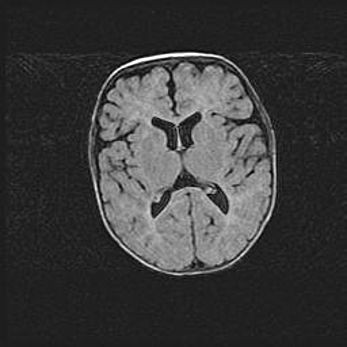

Церебральная ишемия II.

Возраст: 5 дней

Вес: 3400 г

Пол: женский

Окружность головы: 35 см

Срок гестации: 39 недель

Церебральная ишемия – это заболевание, характеризующееся недостаточностью (гипоксией) либо полным прекращением (аноксией) снабжения мозга кислородом по причине закупорки одного или нескольких сосудов. Это приводит к  что метаболическим расстройствам различной степени тяжести в тканях головного мозга, развитию коагуляционных некрозов и гибели нейронов.